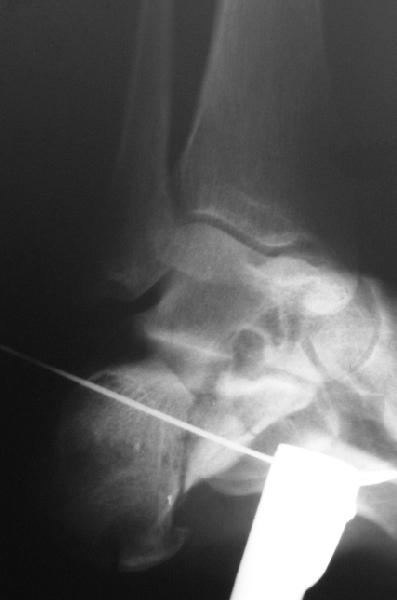

Накладываем спицевой дистрактор, позволяющий выхаживать м/ткани и одновременно устранять захождение отломков.